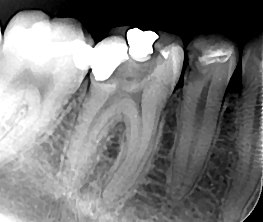

Lečenje zuba predstavlja skup terapijskih mera kojima se tretira unutrašnjost zuba, odnosno mesto gde se nalazi zubna pulpa (zubni živac). Zavisno od stanja zubne pulpe, odnosno da li su u zubni kanal dospeli mikroorganizmi ili ne, lečenje zuba se može obaviti u jednoj ili više seansi. Upotrebom opreme za digitalno određivanje radne dužine i mašinsku obradu kanala korena skrajućuje se vreme postupka i komplikacije nakon intervencije svode na minimum.

Zubni kanal neophodno je obraditi dezinfikovati i trodimenzionalno hermetički zatvoriti. Tako se sprečava prodor bakterija iz usne duplje preko zubnog kanala do koštanog tkiva vilica.